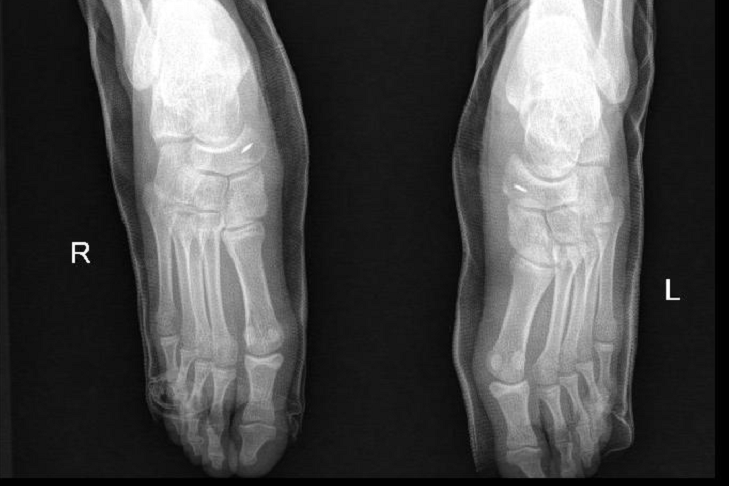

【术后复查x线显示:双足副舟骨已切除,胫后肌腱重建处可见铆钉固定】